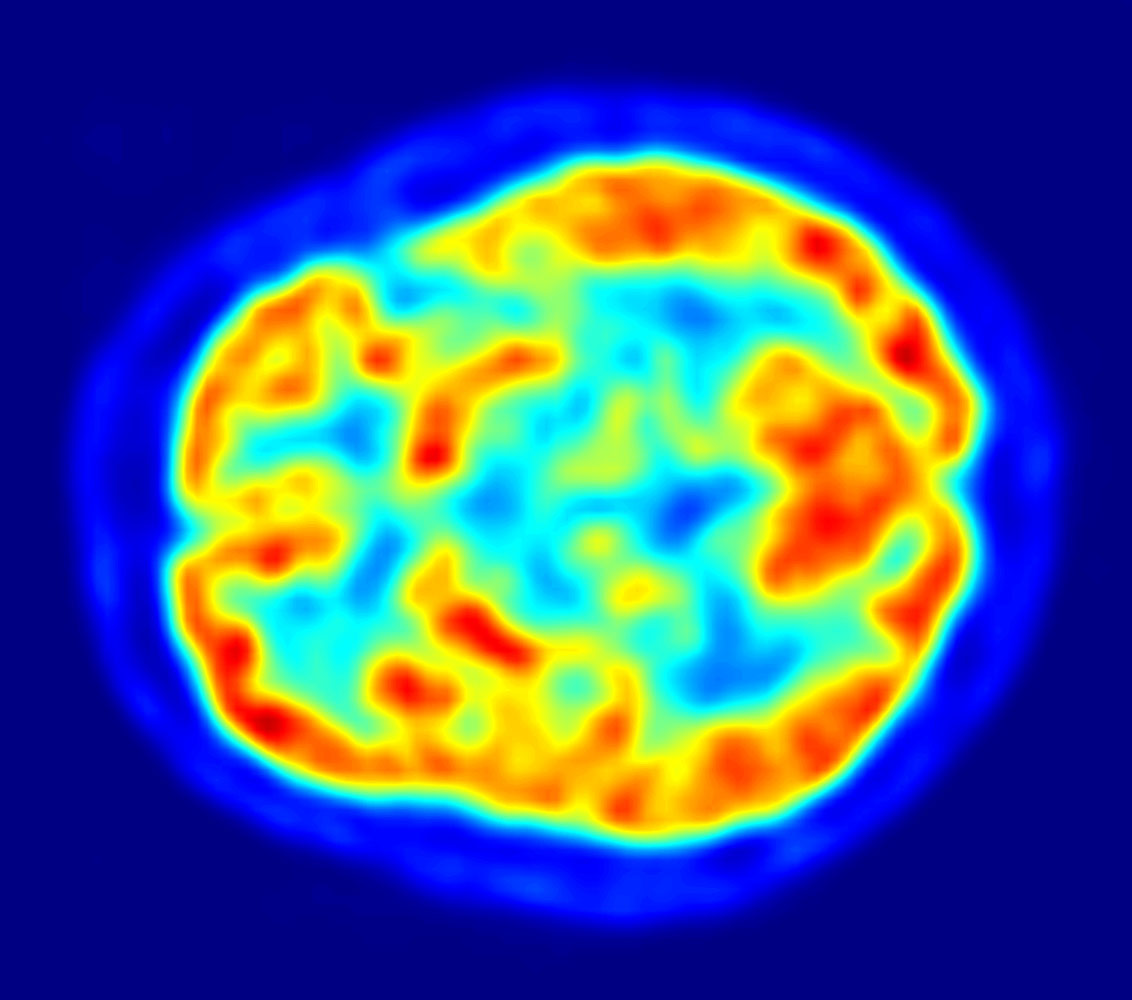

1980년대 N400 (신경과학)의 발견과 함께 뇌파(EEG) 및 뇌자도(MEG)와 같은 전기생리학적 기술이 언어 연구에 도입되었다.[11][12] 최근에는 양전자 방출 단층 촬영술(PET), fMRI 등 뇌 영상 기술의 발전으로 언어 처리와 관련된 뇌 영역 및 활성화 패턴에 대한 이해가 높아지고 있다.[3][10][28]

최근 뇌 기능 영상 기법(양전자 방출 단층 촬영술(PET), fMRI 등)의 발달로 언어 처리 시 뇌 활동을 높은 공간 해상도로 관찰할 수 있게 되면서, 신경언어학 연구 분야는 크게 확장되었다. 이러한 뇌 영상 기법은 실어증학의 연구 결과와 일치하며, 언어 기능의 해부학적 기반을 밝히는 데 기여하고 있다.[3]

- 뇌 기능 영상 기술: 양전자 방출 단층 촬영술(PET)과 기능적 자기 공명 영상(fMRI)은 뇌의 특정 영역에 산소를 공급하기 위해 혈액이 보내지는 현상을 이용하여 뇌 활동 위치를 정확하게 파악한다.[3] 이러한 기술들은 특정 언어 작업을 수행하는 뇌 영역뿐만 아니라, 언어 노출에 따라 뇌의 언어 구조와 관련 활성화 분포가 시간이 지남에 따라 어떻게 변하는지도 보여준다.[19][30][31][24]

PET과 fMRI는 뇌의 특정 영역에 산소를 공급하기 위해 혈액이 보내지는 현상(혈액 산소 레벨 의존성, 또는 BOLD 반응)을 이용한다.[27] 이러한 기술은 높은 ''공간 해상도''를 제공하여 뇌 내 활동 위치를 정확히 찾아낼 수 있게 해주지만,[3] ''시간 해상도''(뇌 활동 타이밍에 대한 정보)는 좋지 않다.[28][29] PET 및 fMRI는 특정 언어 과제 또는 계산을 수행하는 뇌 영역을 보여줄 뿐만 아니라,[19][30] 언어적 노출에 따라 뇌의 언어 구조와 언어 관련 활성화 분포가 시간이 지남에 따라 어떻게 변하는지도 보여준다.[31][24]